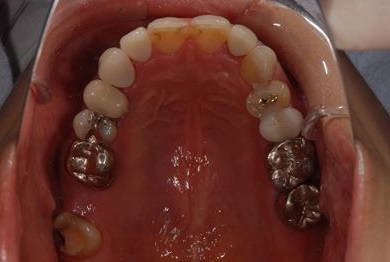

| 性別/年齢 | 女性 / 34歳 | ||||||||||||||||||||||||||||||||

| 治療方針 | 上前歯部分、セラミック治療にて審美的回復を行う。 | ||||||||||||||||||||||||||||||||

| 治療内容 | オールセラミッククラウン3本(オールセラミック用土台3本)、メタルボンドセラミッククラウン1本 | ||||||||||||||||||||||||||||||||

| 総治療費 | 562,800円 | ||||||||||||||||||||||||||||||||

| 治療期間 | 8ヶ月 |